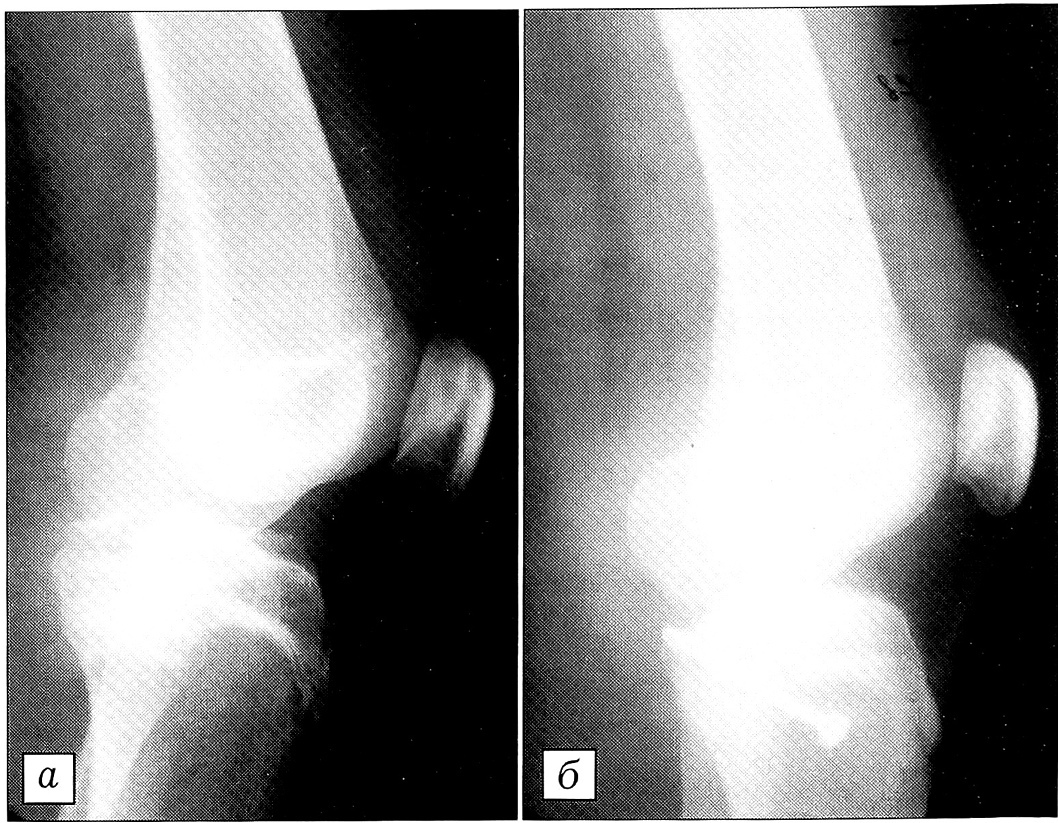

Больной М.,36 лет, получил травму коленного сустава при автоаварии (сбит автомобилем). Поступил с выраженным болевым синдромом и отеком. На рентгенограмме выявлен отрывной перелом задневерхнего края большеберцовой кости (рис. 2, а). Фрагмент сравнительно небольших размеров, однако смещение его превышает 1 см. При поступлении выполнены пункция коленного сустава, местная анестезия. Выявлен положительный симптом «заднего выдвижного ящика». Поврежденный сустав фиксирован гипсовой шиной. На 5-е сутки после травмы произведена открытая репозиция из заднего доступа и фиксация фрагмента костным швом (рис. 2, б). В течение 6 нед после операции продолжалась иммобилизация гипсовой шиной, затем проводились ЛФК и массаж, дозированная нагрузка. Пациент осмотрен через 4 года: жалоб нет, сустав стабилен, объем движений полный.

Рис. 2. Рентгенограммы коленного сустава больного М. до (а) и после (б) операции.